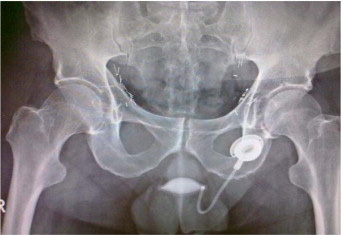

Mirena IUD embeded in uterusA South Dakota woman was recently awarded $3.35 million in the first of 2,100 vaginal mesh lawsuits. They jury will now weigh punitive damages that may total as much as $16.75 million.